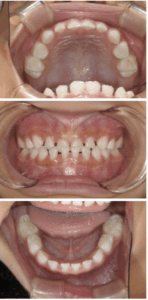

【 Before 】

〈 年齢・性別 〉 5歳 女児

〈 主訴・相談内容 〉 反対の噛み合わせを改善したい

〈 診断名 〉 前歯部反対咬合

〈 装置 〉 プレオルソタイプ3

〈 抜歯部位 〉 非抜歯

〈 治療期間 〉 1年で改善、その後経過観察(3年間)

〈 治療費 〉 110,000円 (税別・精密検査代別)

〈 治療のリスク 〉 治療後の後戻り